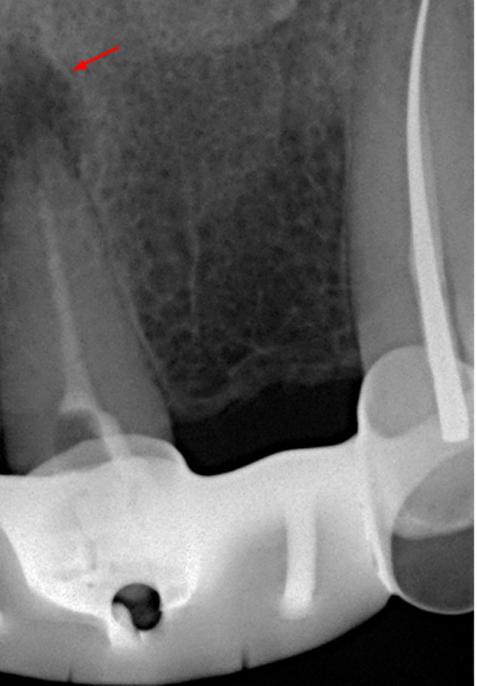

Выявлена болезненность при перкуссии и пальпации в области 21 зуба. Зуб не реагирует на термические раздражители. Результаты пародонтологического обследования в пределах нормы, рентгенологическое обследование выявило радиолюцентную зону в области верхушки корня (снимки 1, 2).

Диагноз: Острый апикальный периодонтит.